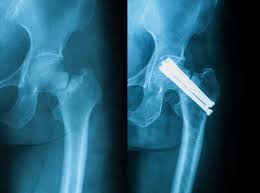

Oberschenkelhalsbruch alte menschen tot. Ein Oberschenkelhalsbruch kann für alte Menschen das Sterberisiko erhöhen. Diese Einteilungen dienen der Therapieentscheidung und Prognoseabschätzung. Mit zunehmendem Alter nimmt die Knochendichte der Knochen ab und somit auch die Stabilität.

Das soll sich ändern. In den meisten Fällen ist eine Operation notwendig. Auch ist der Knochen häufig durch Osteoporose vorbelastet und bricht schon bei geringer Gewalteinwirkung.

Schon ein einfacher Sturz kann bei ihnen zum Oberschenkelhalsbruch fachl. Der Oberschenkelhalsbruch ist eine gefürchtete Folge von Stürzen da er meist eine Operation nach sich zieht und einen erheblichen Einschnitt ins Leben bedeuten kann. Der Oberschenkelhalsbruch gehört zu den fünf großen gesundheitlichen Problemen älterer Menschen.

In der Regel verstirbt man gerade nach einem Oberschenkelhalsbruch nicht am Bruch an den Keimen oder einer Lungenentzündung die man sich erst im Krankenhaus einfängt. Der Oberschenkelhalsbruch ist eine häufige Verletzung bei alten und sehr alten Menschen. Die Verletzten können keinen Schritt mehr gehen und sind nicht in.

Der Oberschenkelhalsbruch ist das Krankheitsbild des alten Menschen und ist in der Regel durch den Sturz auf die Seite verursacht.

Ein Oberschenkelbruch bedeutet für ältere Menschen häufig das Ende der Selbständigkeit. Auch ist der Knochen häufig durch Osteoporose vorbelastet und bricht schon bei geringer Gewalteinwirkung. Gefährlich für alte Menschen sind auch Schlafmittel weil sie die Reaktionsfähigkeit herabsetzen und damit ebenfalls das Sturzrisiko steigern etwa beim nächtlichen Gang zur Toilette. Wenn man von einem Oberschenkelhalsbruch hört denkt man meist an alte Menschen. Bislang stirbt jeder Fünfte über 70 Jahren nach einer OP. Ein Oberschenkelbruch bedeutet für ältere Menschen häufig das Ende der Selbständigkeit. Zudem ist es sinnvoll mögliche Grunderkrankungen die zu einer erhöhten Sturzgefahr führen wie zum Beispiel Osteoporose Knochenschwund Schwindel zu behandeln. Ein Oberschenkelhalsbruch trifft meist ältere Menschen. Die Verletzten können keinen Schritt mehr gehen und sind nicht in.

Ein Oberschenkelbruch bedeutet für ältere Menschen häufig das Ende der Selbständigkeit. Die Sterblichkeit ist erheblich viele. Bislang stirbt jeder Fünfte über 70 Jahren nach einer OP. Welche Symptome deuten auf einen Oberschenkelhalsbruch hin. Ein Oberschenkelhalsbruch trifft meist ältere Menschen - oft mit fatalen Folgen. Der Oberschenkelhalsbruch ist eine häufige Verletzung bei alten und sehr alten Menschen. Wenn man von einem Oberschenkelhalsbruch hört denkt man meist an alte Menschen.